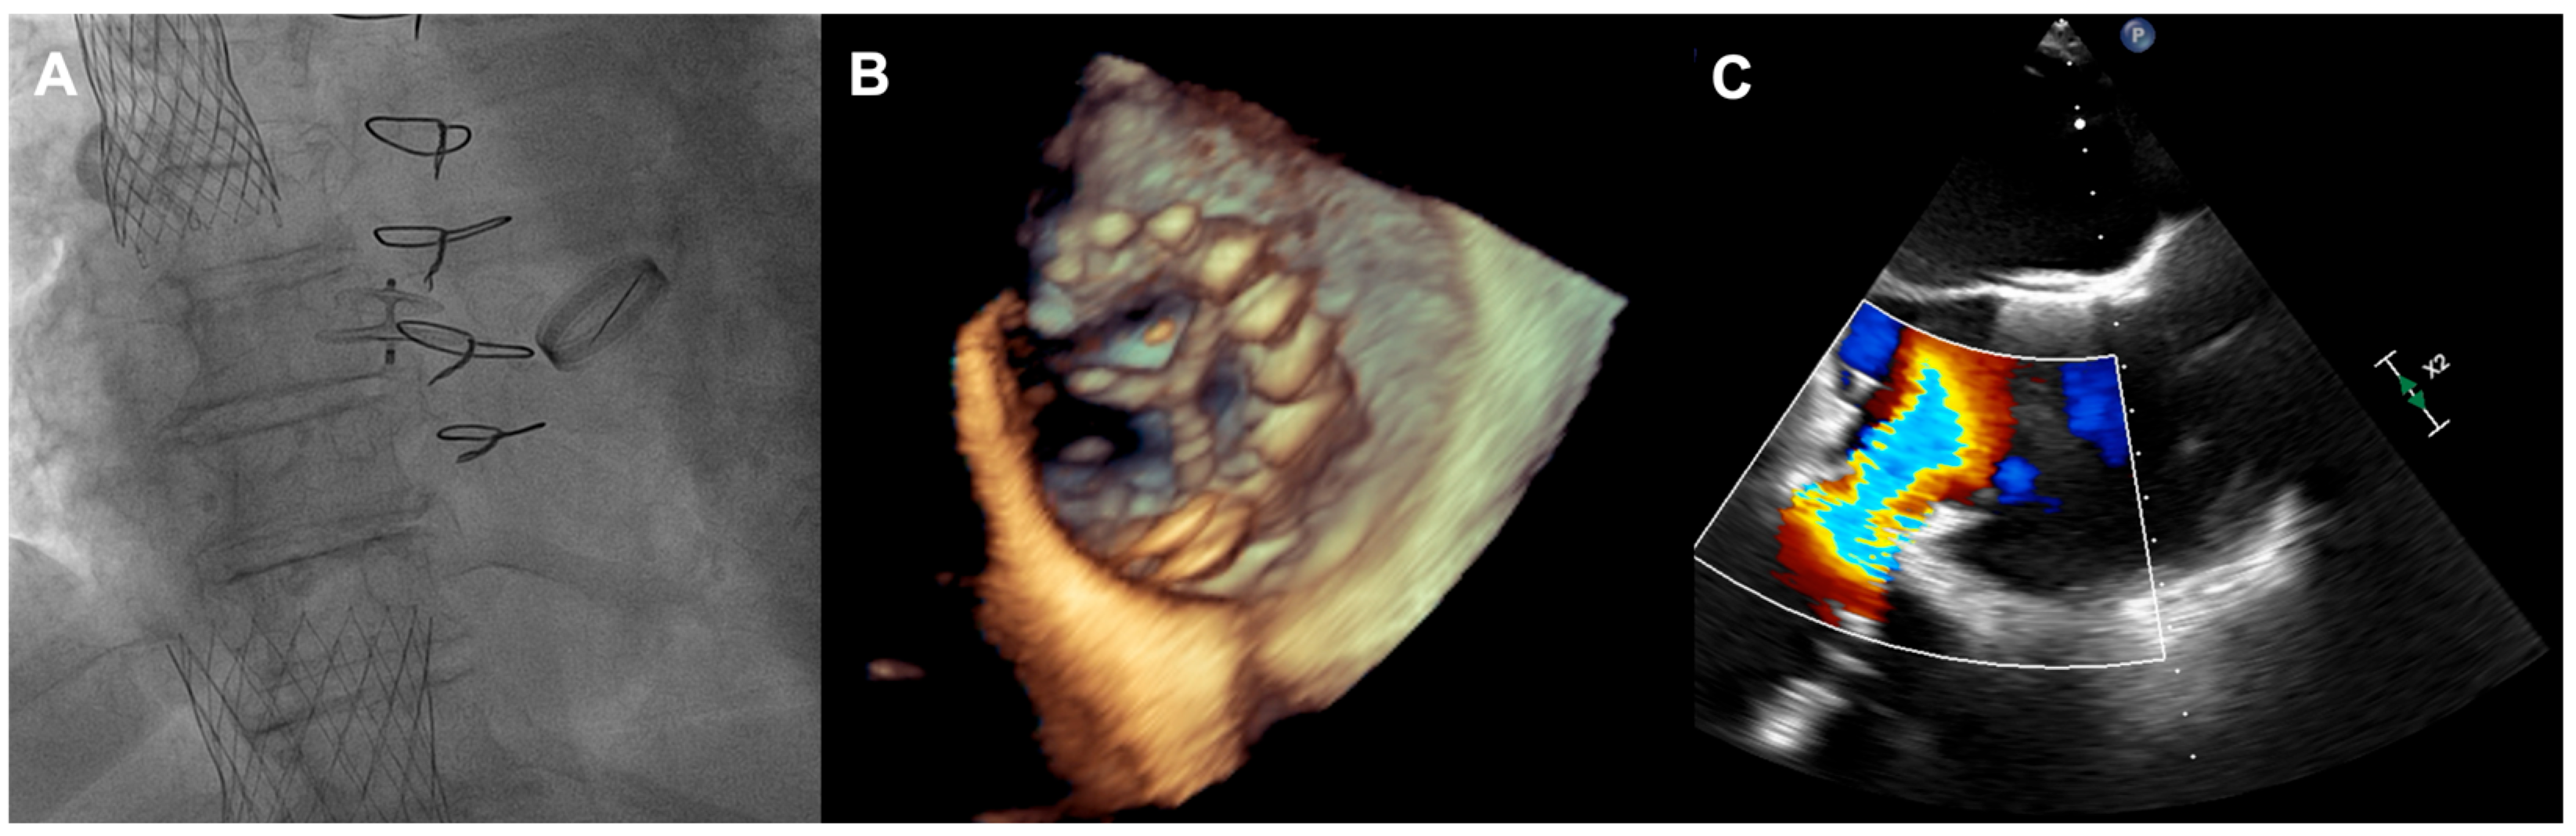

A 73-year-old woman with a history of two surgical interventions—an aortic valve replacement 25 years before and a thoracic aortic aneurysm repair 12 years before—was admitted to the hospital because of persistent heart failure symptoms in functional class NYHA III, accompanied by peripheral edema and ascites. The transthoracic echocardiography showed preserved function of the mechanical aortic prosthesis and torrential TR with tricuspid anulus enlargement. A further transesophageal examination revealed a large, mainly central coaptation deficit between the tricuspid leaflets, located mainly in the central region of the valve (Figure 3). Furthermore, a patent foramen ovale (PFO) with spontaneous right-to-left shunt was also diagnosed. Due to the valve anatomy, the patient was not deemed eligible for the transcatheter edge-to-edge repair. Because of the symptoms’ persistence, a two-step percutaneous procedure was planned. First, the PFO was closed with the 25 mm Amplazer occluder. Two weeks later, the CAVI procedure with the implantation of TricValve system valves (SVC 29 mm; IVC 45 mm) was carried out without complications. (Figure 4) We believed that the PFO closure was necessary before the CAVI procedure because the implantation of venae cavae valves in a patient with a patent PFO would have caused an exacerbation of the right-to-left shunt and possible patient desaturation. In observation, six and twelve months after the procedure, the patient remained on stable doses of oral diuretics and was considered to be in NYHA functional class II, without worsening heart failure or requiring hospitalization.

Figure 4. (A) Final angiographic result of TricValve implantation; (B) 3D view of IVC valve protruding to RA; (C) inflow from IVC through the implanted valve. IVC—inferior vena cava; RA—right atrium.